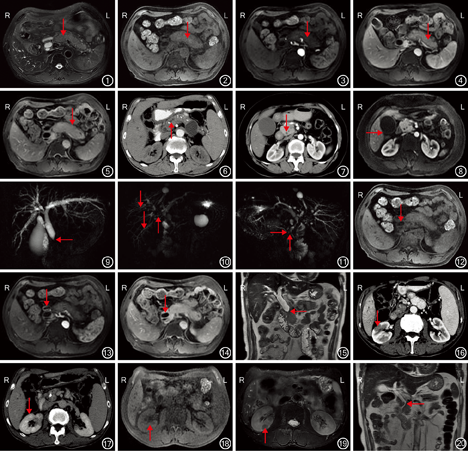

21例患者中,17例行CT检查,11例行MRI检查(其中7例联合行CT检查)。胰腺表现:(1)胰腺密度和信号:MRI检查示胰腺弥漫性增大14例,胰腺正常羽毛状结构及花边消失,边缘饱满,呈"腊肠样"改变(图1)。CT平扫呈均匀等密度影,增强扫描动脉期强化程度减低,门静脉期及延迟期逐渐均匀强化,边缘未见强化。MRI平扫病灶T1加权成像呈稍低信号,T2加权成像呈稍高信号,DWI呈高信号,增强扫描呈延迟强化,病灶边缘T1、T2加权成像均呈稍低信号,增强未见强化(图2,图3,图4,图5)。(2)胰腺萎缩和钙化:3例胰腺实质萎缩,内见散在钙化(图6)。(3)胰腺增大:4例胰腺局限性增大呈"假肿瘤样"改变,其中胰头部局限性增大2例(图7,图8)。(4)胰管改变:MRCP检查示4例表现为胰管弥漫性狭窄,3例表现为局限性狭窄,1例局限性扩张(图6)。

胰腺外表现:MRCP检查示11例患者表现为胆道系统改变,可见肝内胆管及胆总管扩张,部分狭窄,胆管壁广泛增厚(图9,图10,图11),MRI增强扫描检查示胆管壁呈明显强化(图12,图13,图14)。4例患者行MRCP检查可见胆总管末段呈"鸟嘴样"狭窄(图15)。3例患者表现为肾脏改变,CT增强扫描检查动脉期可见肾脏斑片状低密度影(图16),延迟期斑片状低密度影均匀强化(图17),MRI平扫T1抑脂序列图像示肾脏病灶呈等信号(图18),T2抑脂序列图像呈斑片状低信号(图19)。实质期及延迟期病灶逐渐均匀强化。

CT检查确诊11例,诊断准确率为11/17。MRI检查确诊8例,诊断准确率为8/11。1例患者CT及MRI检查均误诊为胰头癌(图7,图8),1例MRI检查误诊为胆总管下段癌(图20)。